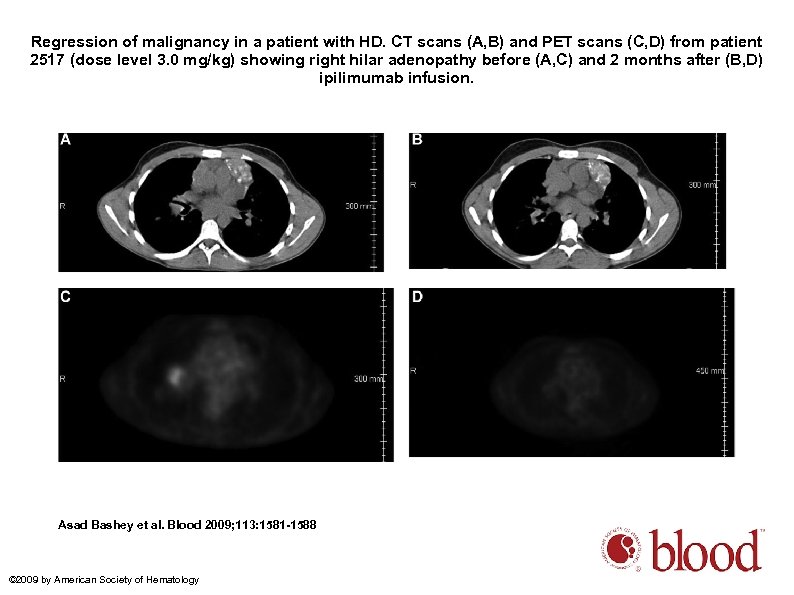

Regression of malignancy in a patient with HD. CT scans (A, B) and PET scans (C, D) from patient 2517 (dose level 3. 0 mg/kg) showing right hilar adenopathy before (A, C) and 2 months after (B, D) ipilimumab infusion. Asad Bashey et al. Blood 2009; 113: 1581 -1588 © 2009 by American Society of Hematology